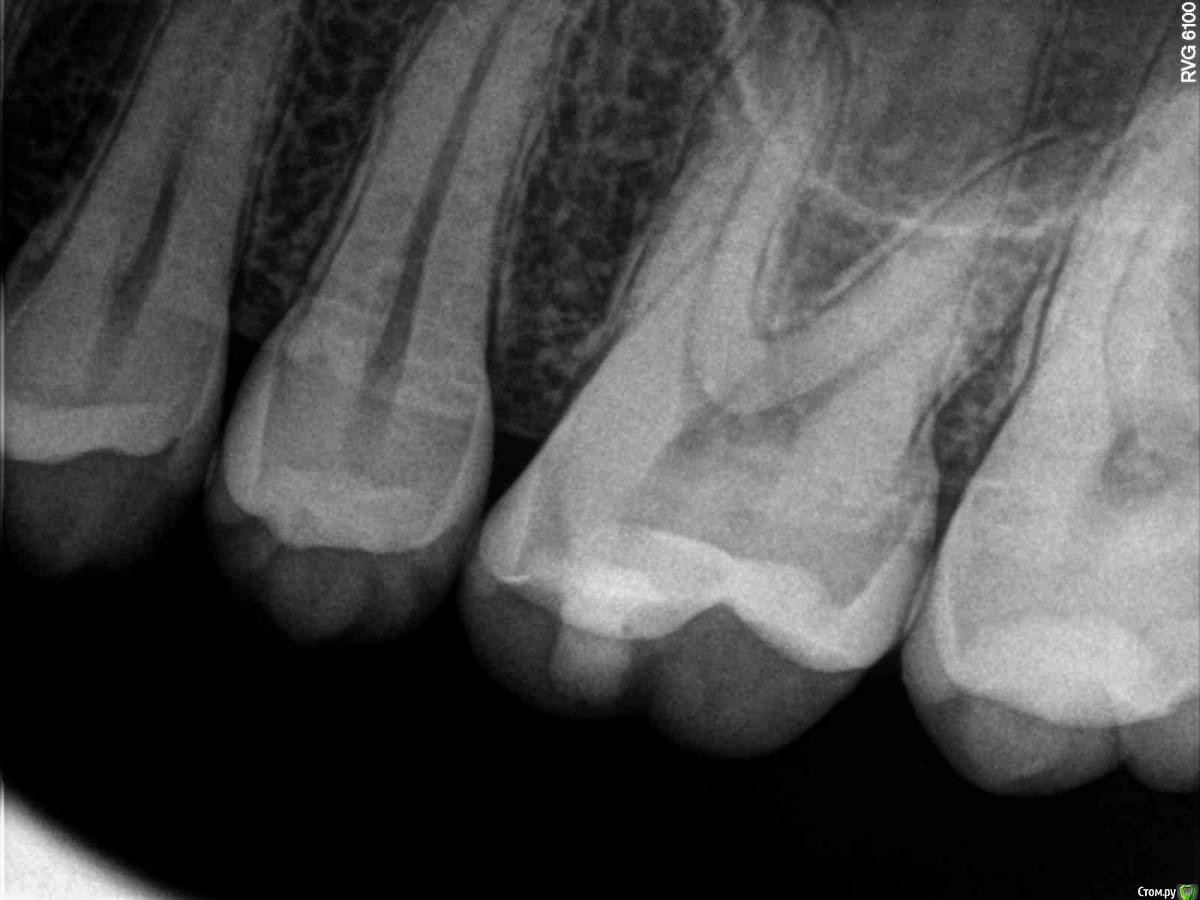

SolnceSamara Опубликовано 24 октября, 2015 Поделиться Опубликовано 24 октября, 2015 почернела старая пломба в давно пролеченной шестерке (сверху). Врач заменила пломбу но зуб болел при надавливании, заменили пломбу повторно-все равно осталась боль, сменила врача-снова сменили пломбу-снова болит, решили депульпировать-снова вынули пломбу, поставили временную-неделю проходила с временной-через неделю окончательно депульпировали, поставили постоянную. Сначало поболело 3 дня, и вроде прошло, хотя остался дискомфорт при надавливании. Прошло 3 недели, боль усилилась, теперь болит не только при надавливании иногда просто звеняще-ноющее ощущение нарастает. Пью нимесил. Посоветуйте что делать-что не так? Снимки прилагаю-делали на протяжении всйх операций (до и после).Разьяснение по снимкам :R1-29/08/15R2,R3-25/09/15R4-R7-28/09/15 Ссылка на комментарий

red_butler Опубликовано 24 октября, 2015 Поделиться Опубликовано 24 октября, 2015 Коллеги поправят, но выглядит как пломбирование одиночным штифтом. Возможно пропущен четвертый канал. Нужна ревизия корневых каналов. 2 Ссылка на комментарий

DmitrySH Опубликовано 24 октября, 2015 Поделиться Опубликовано 24 октября, 2015 Коллеги поправят, но выглядит как пломбирование одиночным штифтом. Возможно пропущен четвертый канал. Нужна ревизия корневых каналов. Все верно. Ссылка на комментарий